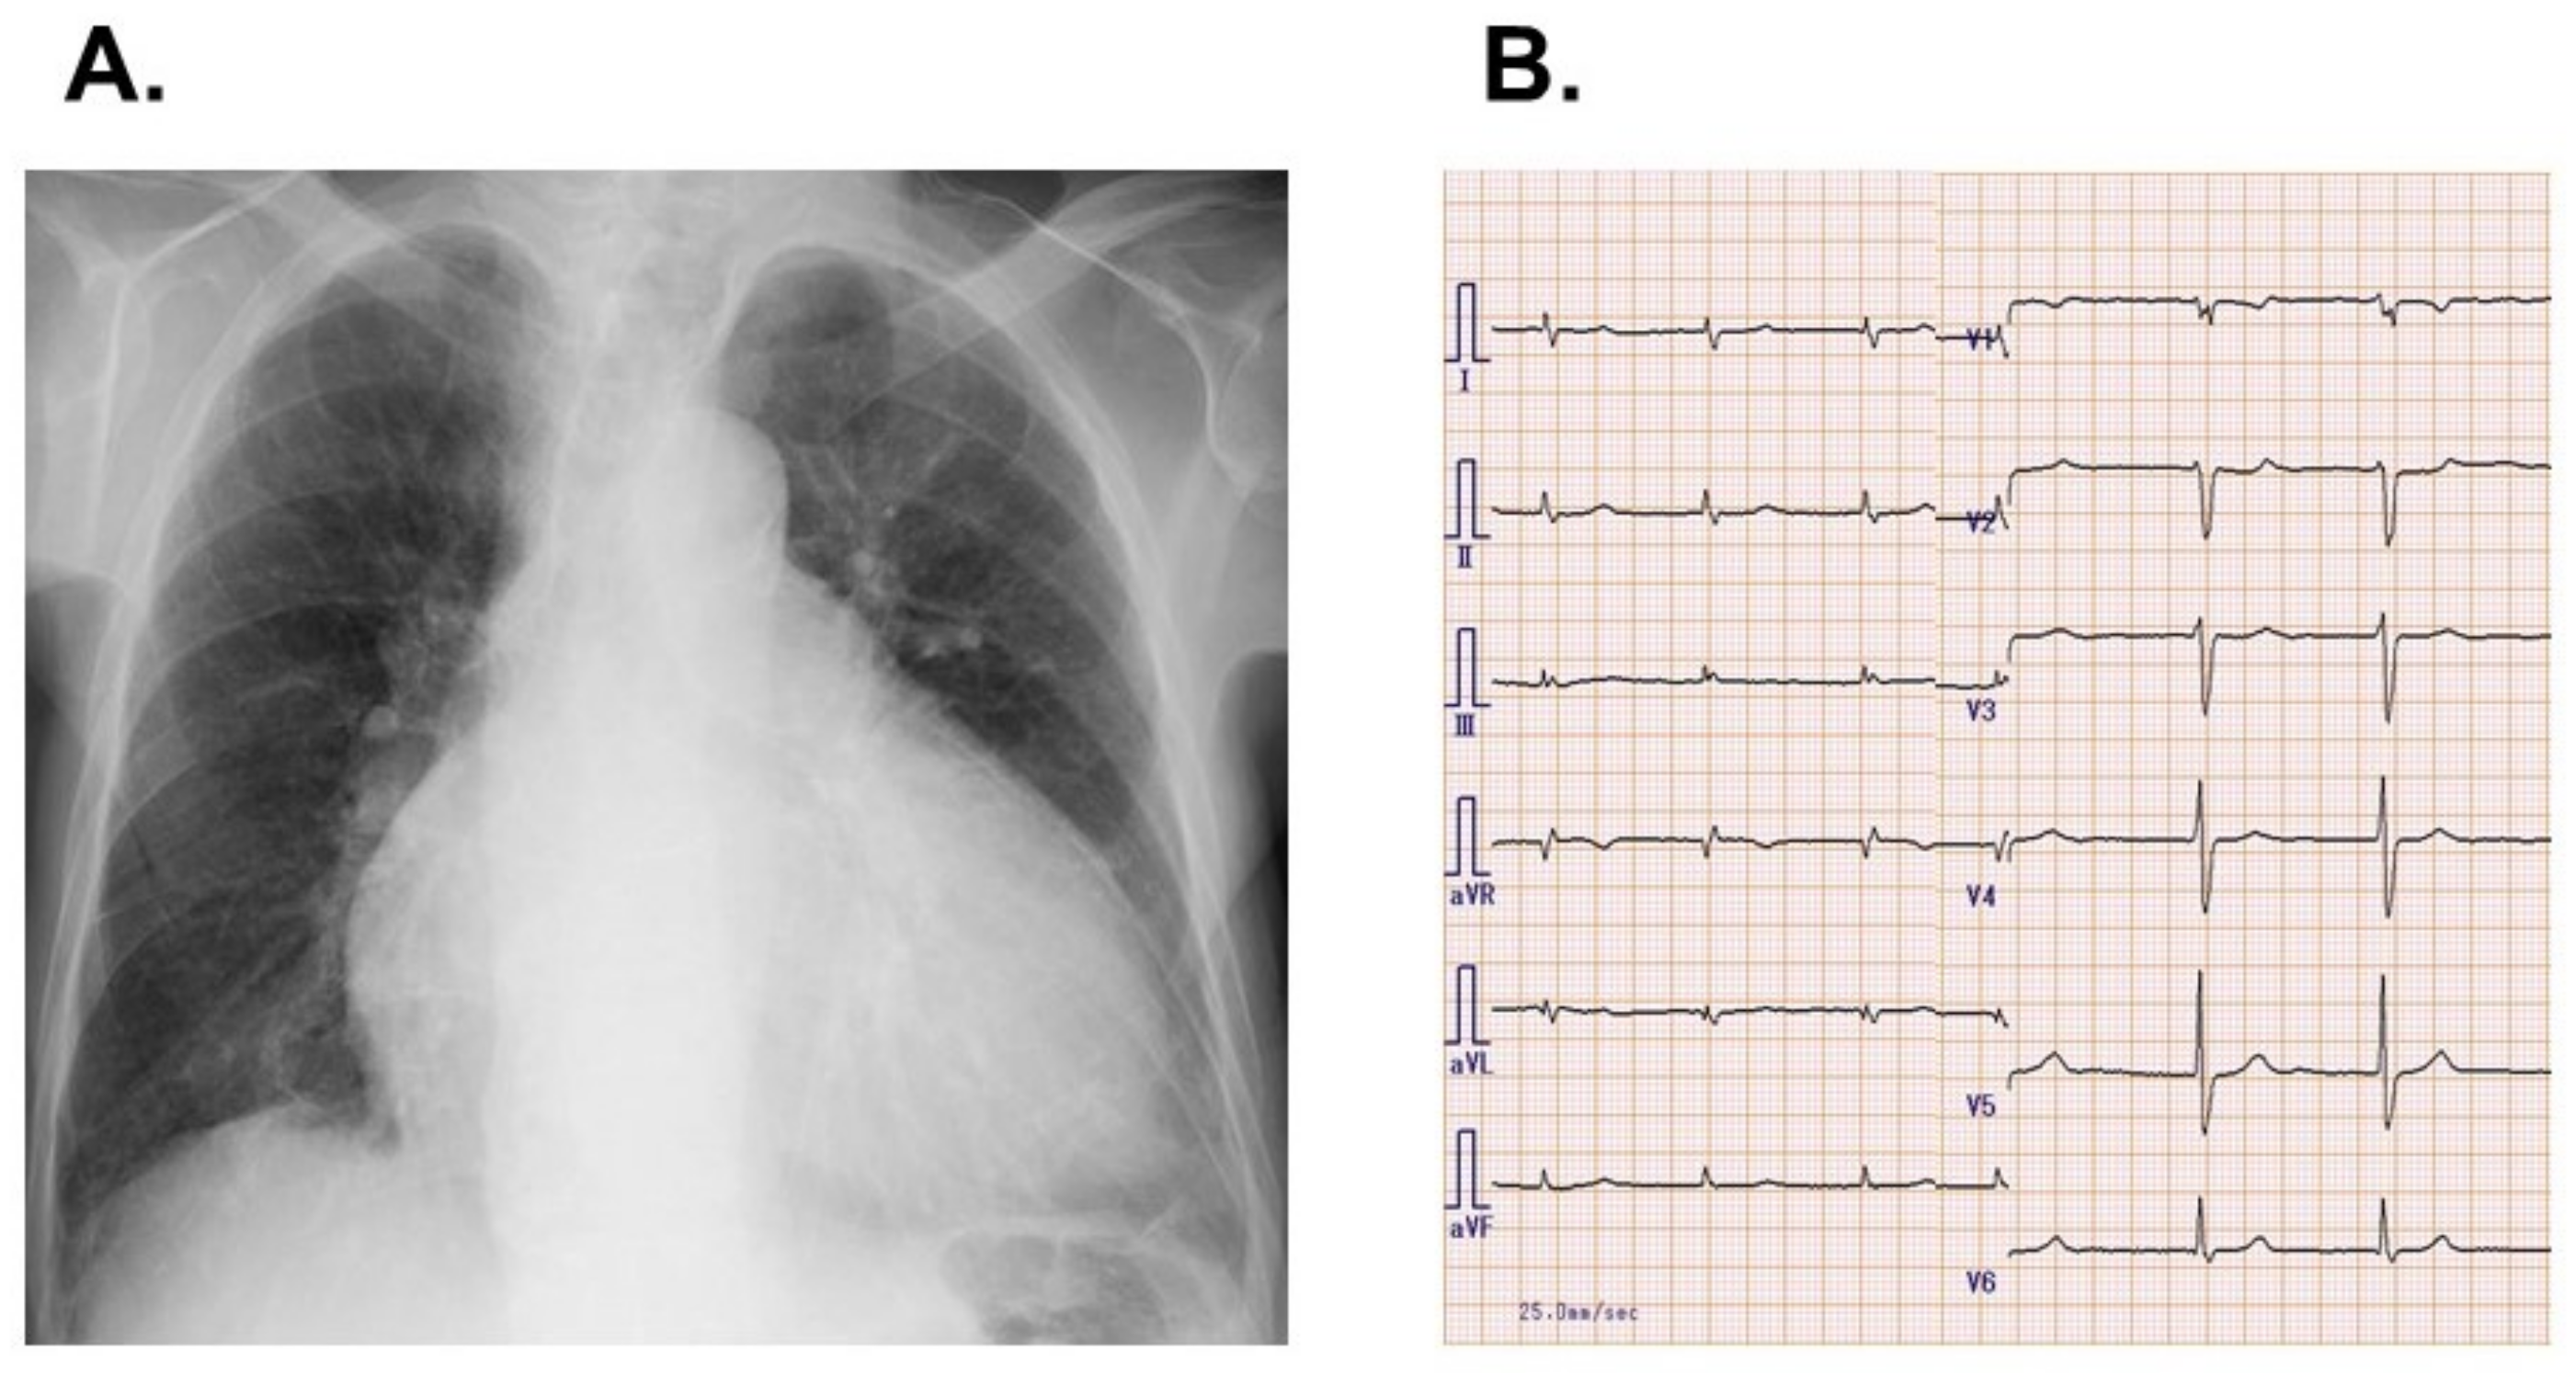

2.1. On Admission